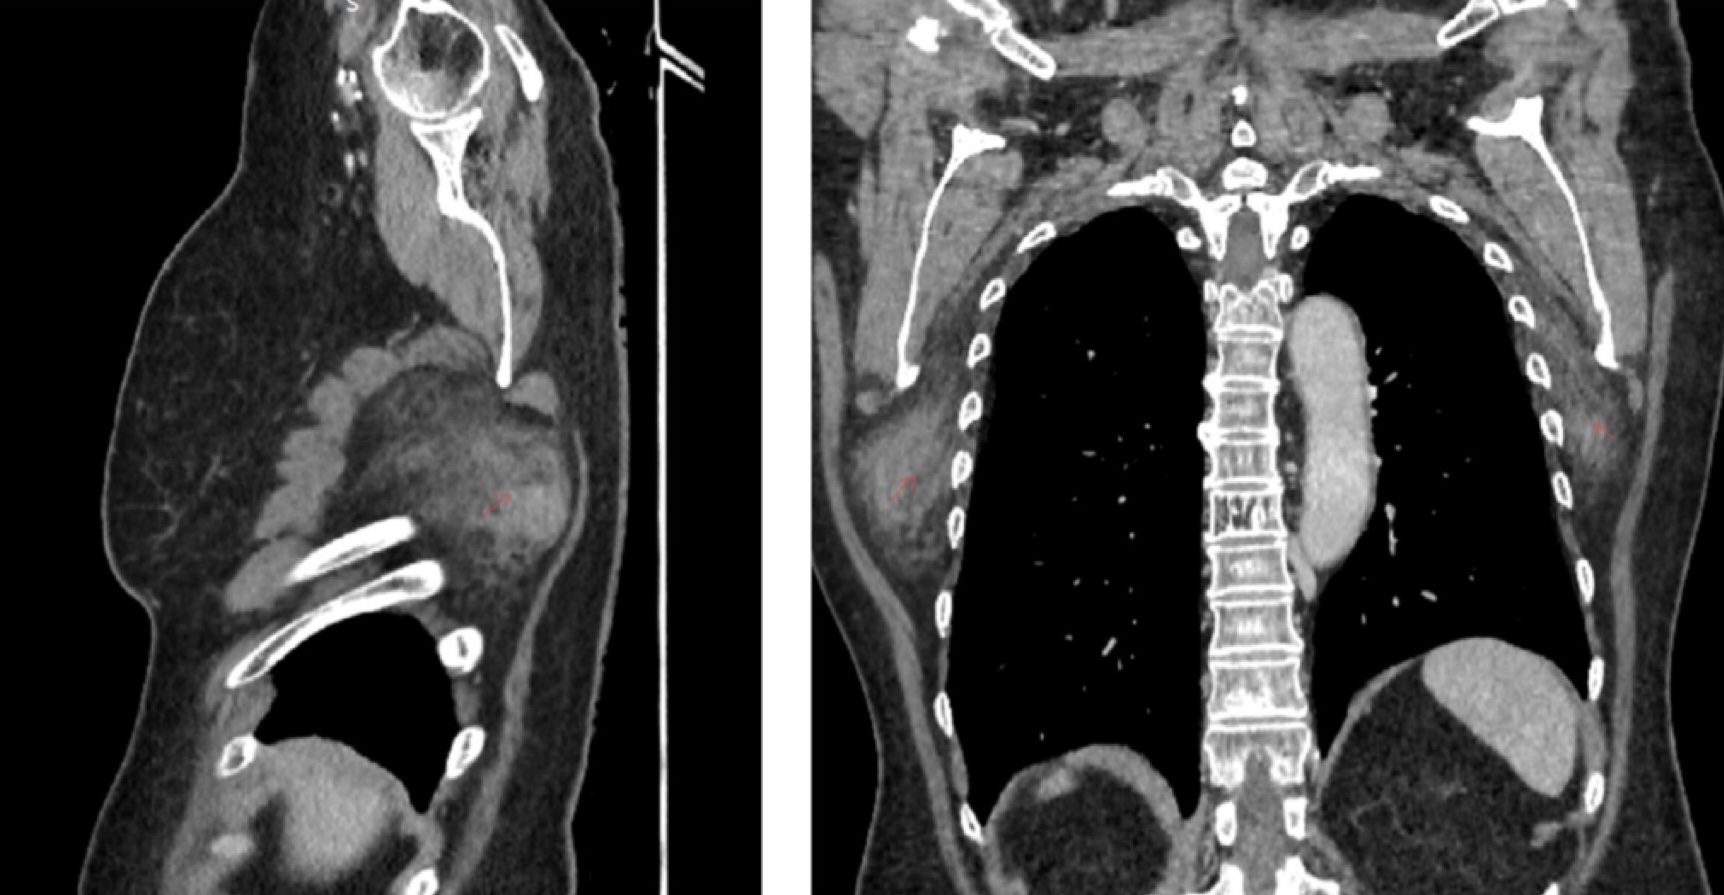

Computed tomography findings may be highly suggestive of this pathology, most commonly showing a poorly defined soft-tissue mass with attenuation similar to the adjacent skeletal muscle and having internal striations or scattered areas of fat. Studies show that the smaller the tumor, the more homogenous attenuation will show on a computed tomography scan.5

Similar characteristics have been shown on our patient’s computed tomography scan; the tumors were situated posterior to the serratus muscles and anterior to the latissimus dorsi and scapular plane (Figures 1 and 2).

Figure 1. Computed tomography scan of the patient showing the 2 tumors situated anterior to the scapular plane.

Figure 2. Computed tomography scan from an anterior and lateral perspective.